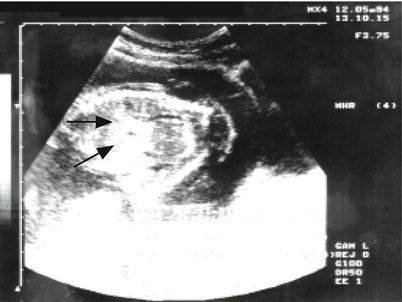

Fig. 15.15

Hyperechoic image observation corresponding to an intestine (black arrows) in a longitudinal cross-section of the fetal abdomen at the level of the liver, in a case of suspected cytomegalovirus